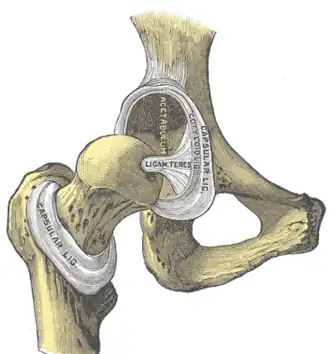

Hip-joint, front view. The capsular ligament has been largely removed. (Capsular ligament visible at center.) | |

Anterosuperiorly, it is attached to the margin of the acetabulum 5 to 6 mm beyond the labrum behind; but in front, it is attached to the outer margin of the labrum, and, opposite to the notch where the margin of the cavity is deficient, it is connected to the transverse ligament, and by a few fibers to the edge of the obturator foramen.

The longitudinal fibers are greatest in amount at the upper and front part of the capsule, where they are reinforced by distinct bands, or accessory ligaments, of which the most important is the iliofemoral ligament.

The other accessory bands are known as the pubofemoral ligament and the ischiofemoral ligament.